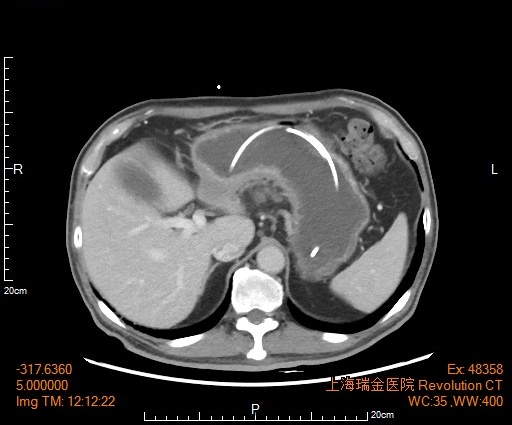

经过3个周期化疗,影像报告显示,老沈肿瘤体积明显缩小,原本存在的转移灶全都消失。营养状况也明显好转,血红蛋白恢复了正常。刘文韬医生团队为老沈做了根治性胃癌切除手术,他很快可以正常饮食,出院回家了。更令人欣喜的是,病理报告提示,癌细胞消失了!显微镜下找不到一点癌细胞的残留。

前后对比肿瘤变化